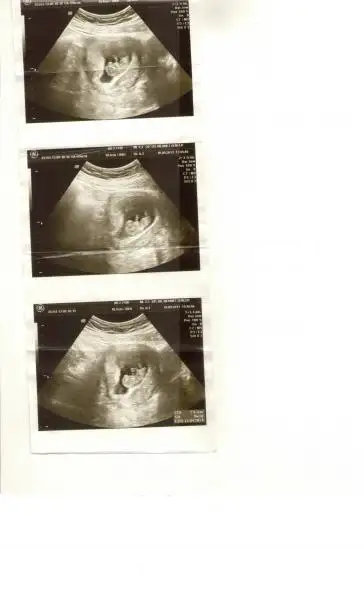

rica etsem benim bebeğimede bakabilirmisiniz lütfennn :)Eki Görüntüle 811667 Eki Görüntüle 811668

tam yükleyemedim galiba anlayamazsanız tekrar yüklerim